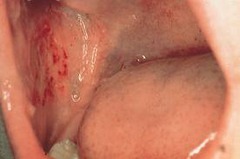

Elongated, raised, firm, pink lesion adjacent to denture boarder; seen in denture wearers; caused by ill fitting denture